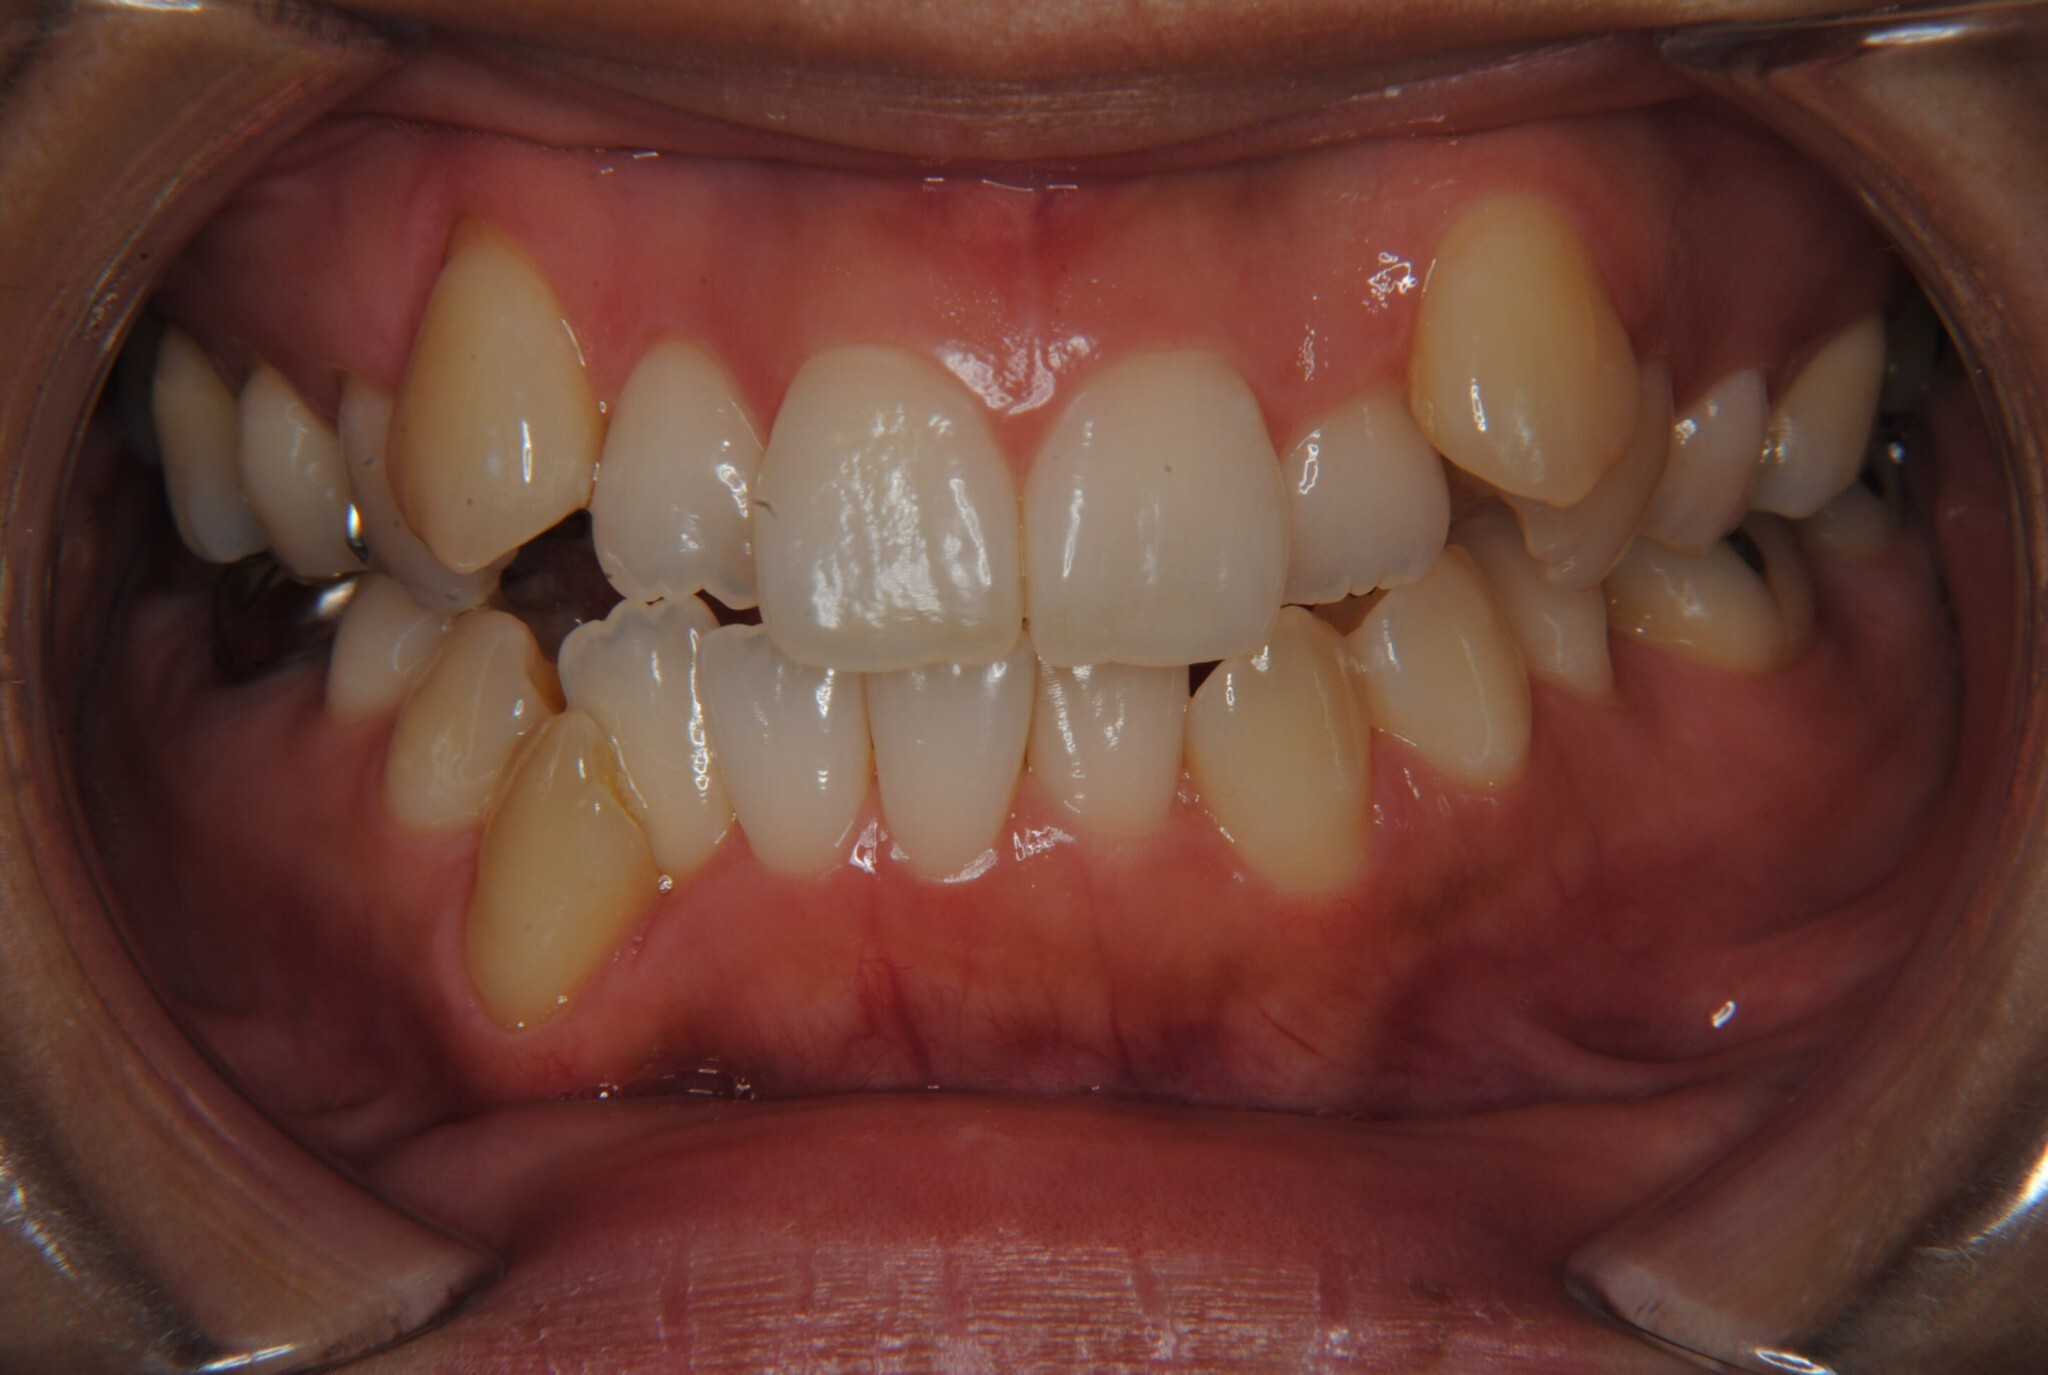

①主訴:八重歯、前歯のガタガタ、真ん中の不一致を治したい

②診断名:AngleⅠ級叢生

⑤抜歯部位:上下左右第一小臼歯